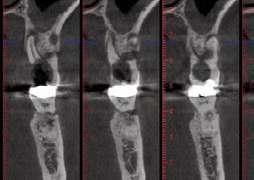

17.- Verificamos nuestro tratamiento con CBCT.

El diente 11 fue extraído (Figura 4), seguido por la preservación alveolar. Se realizó un injerto pediculado de espesor parcial rotado del paladar (Figura 5), junto con una membrana de colágeno reabsorbible, un xeno-injerto bovino y cianoacrilato sellando al alveolo (Figura 6). La provisionalización consistió en un puente adhesivo de resina con dos alas de metal. El alveolo se dejó cicatrizar durante 6 meses, después de los cuales se tomó una impresión digital así como un escáner CBCT (Figura 7). Se llevó

a cabo una planificación digital para una cirugía guiada de implante en una posición protéticamente ideal (Figura 8). El implante 11 se colocó completamente guiado a través de una férula (Figura 9). Las dimensiones del reborde alveolar eran ideales para la colocación del implante en una posición atornillada (Figura 10), al igual que la calidad del hueso cicatrizado. Un injerto de tejido conectivo subepitelial fue estabilizado ocluso-bucalmente al implante (Figura 11) y el puente adhesivo fue recementado (Figura 12). Después de 3 meses de cicatrización, se realizó una restauración provisional y se acondicionó adecuadamente para dar forma al perfil de emergencia, imitando el del diente adyacente (Figura 13). Después de una fase provisional, se tomó una impresión analógica individualizada para el implante 11 y el diente 21 (Figura 14). El laboratorio fabricó una corona implantosoportada de zirconio con cerámica estratificada para el 11 y una carilla laminada feldespática para el diente 21 (Figura 15). Ambas restauraciones fueron colocadas en la paciente y mantenidas. La paciente quedó muy satisfecha con el resultado estético de las restauraciones (Figuras 16, 17). Después de 2 años, el implante permanece saludable con el hueso marginal estable (Figura 18) y una buena calidad y cantidad de tejido blando.

Una correcta planificación digital fue clave para definir los objetivos del tratamiento y el manejo detallado de un caso complejo en una paciente con alta demanda estética. Realizar la preservación alveolar para mejorar las dimensiones volumétricas antes de la colocación del implante facilitó una implantación

guiada sin necesidad adicional de aumento de cresta. La planificación digital con cirugía guiada permitió la implantación en una posición atornillada ideal. La fase de provisionalización consiguió dotar al perfil de emergencia de una apariencia estética y natural. Las dos restauraciones cerámicas resultaron simétricas y muy estéticas para una paciente satisfecha. 